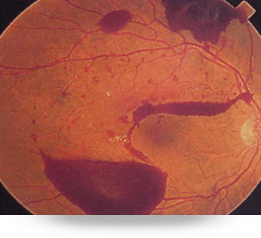

La retinopatía diabética es la principal causa de ceguera en México, debido a que la diabetes produce daño de los vasos sanguíneos, produciendo inflamación de la macula, hemorragias y el desprendimiento de retina llevando a la ceguera.

Todos los pacientes diabéticos tienen que hacerse una revisión del fondo del ojo mínimo una vez al año.

El desprendimiento de retina es un problema muy serio el cual se presenta generalmente en adultos mayores de edad media o avanzada, en personas que presentan miopía alta o antecedentes familiares de este problema.

Un fuerte golpe en el ojo puede provocar un desprendimiento, y en personas que presentan agujeros periféricos en la retina. También la retinopatía diabética puede provocarlo al igual que otras enfermedades inflamatorias.

Las trombosis u oclusiones vasculares de la retina se presentan principalmente en personas mayores de 50 años, especialmente aquellas con hipertensión arterial, diabetes o alguna enfermedad cardiovascular; esta obstrucción arterial o venosa lleva a gran disminución de la visión y se requiere un tratamiento oportuno para evitar la ceguera.